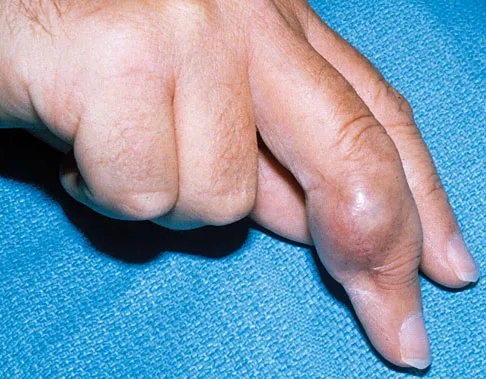

Figure 18a shows the clinical photograph of a 31-year-old man who has a slowly growing nodule on his right middle finger. It is minimally tender, and there is no erythema on examination. A biopsy specimen is shown in Figure 18b. What is the most likely diagnosis?

Explanation

Epithelioid sarcoma is the most common soft-tissue sarcoma in the hand and most commonly occurs in young adults. The tumors can be superficial and may become ulcerated. Deeper lesions are often attached to tendons, tendon sheaths, or fascial structures. These are usually minimally symptomatic. The biopsy specimen reveals the typical appearance of a nodular pattern with central necrosis. They can mimic a necrotizing granulomatous process. Usually there are chronic inflammatory cells along the margin of the tumor nodules. This biopsy specimen does not have the clear cells necessary for a clear cell carcinoma or sarcoma. Nora's tumor is a bizarre parosteal osteochondromatous proliferation (BPOP) first described in 1983 by the pathologist, Nora. The lesion is defined as a reactive heterotopic ossification and is mostly found in the hands or feet of adults in the third decade of life. Enzinger FM, Weiss SW: Soft Tissue Tumors, ed 3. St Louis, MO, Mosby, 1995, p 1074.